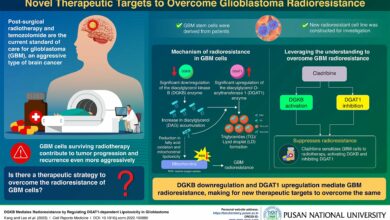

Pesquisadores identificam alvos terapêuticos para superar a radiorresistência de células cancerígenas cerebrais

Pesquisadores da Coréia e dos EUA revelam o mecanismo de radiorresistência, ou resistência à quimioterapia, em células de glioblastoma (câncer…